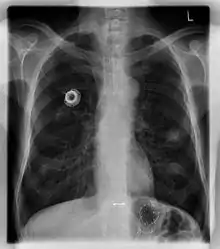

Порти використовуються здебільшого для лікування хворих на гематологічні та онкологічні хвороби. Як правило, його імплантують у верхню частину грудної клітки, трохи нижче ключиці. При цьому катетер вводять у яремну вену.

Порт складається з резервуару, який має силіконову мембрану для введення голки, та катетера. Пристрій вводиться хірургічним шляхом під шкіру, у верхню частину грудної клітки або в руку, і виглядає як ґуля під шкірою. Не вимагає спеціального технічного обслуговування, крім періодичних промивань. Він повністю внутрішній, тому плавання та купання не є проблемою. Катетер проходить від резервуару і хірургічно вводиться у вену (зазвичай яремну вену або менш оптимально підключичну вену). В ідеалі катетер закінчується у верхній порожнистій вені або правому передсерді. Це положення дозволяє швидко та ефективно розподілити влиті препарати по всьому тілу.

Рентгеноскопія корисна для проведення імплантації портів.[1]

Повторна рентгенограма органів грудної клітки може негайно виявити ускладнення, пов'язані з процедурою. Це можуть бути пневмоторакс, гемоторакс або неправильне положення катетера.

Порти можуть бути введені у верхню частину грудей або руку. Точне позиціонування саме по собі є змінним, оскільки його можна встановити, щоб уникнути видимости при носінні сорочок із низьким вирізом, чи щоб запобігти надмірному контакту з рюкзаком або ремінцем бюстгальтера. Найбільш поширене розміщення — у верхній правій частині грудної клітки, при цьому сам катетер проходить через праву яремну вену і вниз до серця пацієнта.